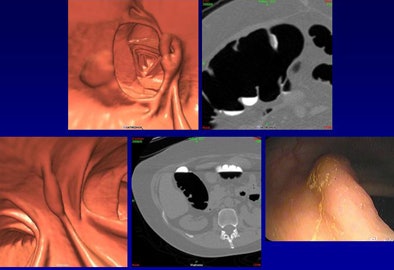

Increased diagnostic confidence and a polypoid (nonflat) morphology both correlated with a higher likelihood of finding a matching lesion at optical colonoscopy, while flat morphology reduced the likelihood of a match at optical colonoscopy, Wise said. Increased diagnostic confidence (level 3 > 2 >> 1) also correlated with a higher positive predictive value.

| The results based on polyp size show that overall PPV greater than 90% varied only slightly between 6- and 9-mm polyps and those 10 mm or larger (top). Below, results based on polyp morphology showed that PPV was higher for pedunculated and sessile polyps versus flat and carpet lesions. Bottom image, results based on diagnostic confidence showed that PPV was significantly higher when the diagnosis was more confident. |